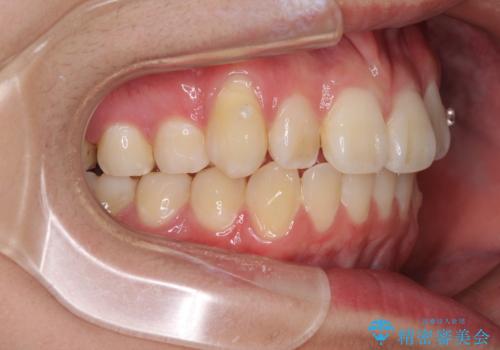

- 八重歯を気にして来院された高校生の患者様です。

ボディーコンタクトの激しい部活動を行っているため、補助装置とインビザラインを用いて、部活動を継続しながら治療を行うこととしました。

八重歯を効率よく改善するため、補助装置を使用して上顎の奥歯を後方に移動させました。

部活動をしながらでしたが、マウスピースをしっかりと装着してくださったので、1年半程度で終了することができました。